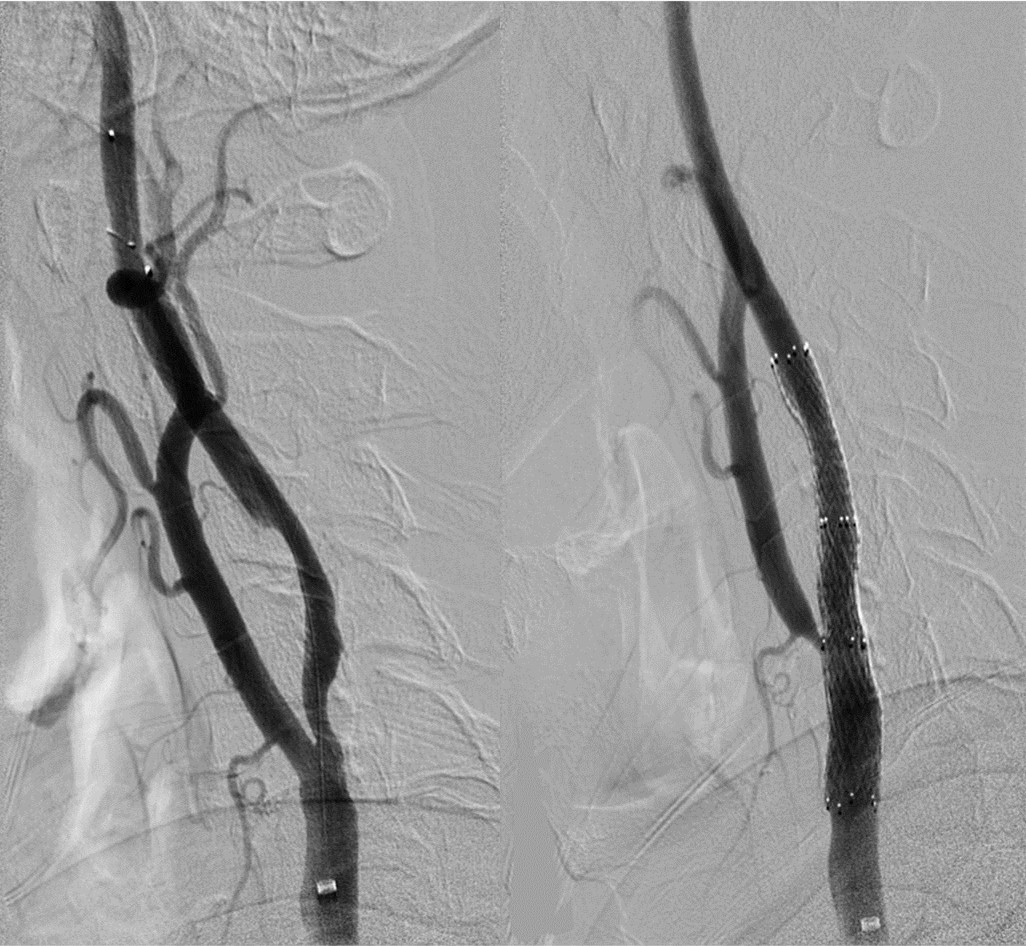

术前CTA提示王先生的主动脉弓形为“牛”型解剖变异(左侧颈总动脉从无名动脉发出,图1),颈总动脉起始部及颈内动脉均存在斑块狭窄,为手术增加了难度,经过仔细讨论分析病情,血管外科吴巍巍主任、赵克强教授决定“另辟蹊径”,从患者右上肢入路,实施微创颈动脉支架手术,同期解决颈总及颈内动脉两处病变。经过充分的术前准备,吴巍巍主任和赵克强教授在麻醉科医师的保驾下联手为王先生安全实施颈动脉微创支架植入术(图3、4),避免了王先生今后再次发生严重的脑卒中事件。术后返回病房,精准调控血压、心率,5天后王先生顺利康复出院。

图2-1 经右上肢造影并建立入路

图2-2  评估颅内情况

图2-3  颈内-颈总动脉植入支架

图2-4 颈总起始植入支架